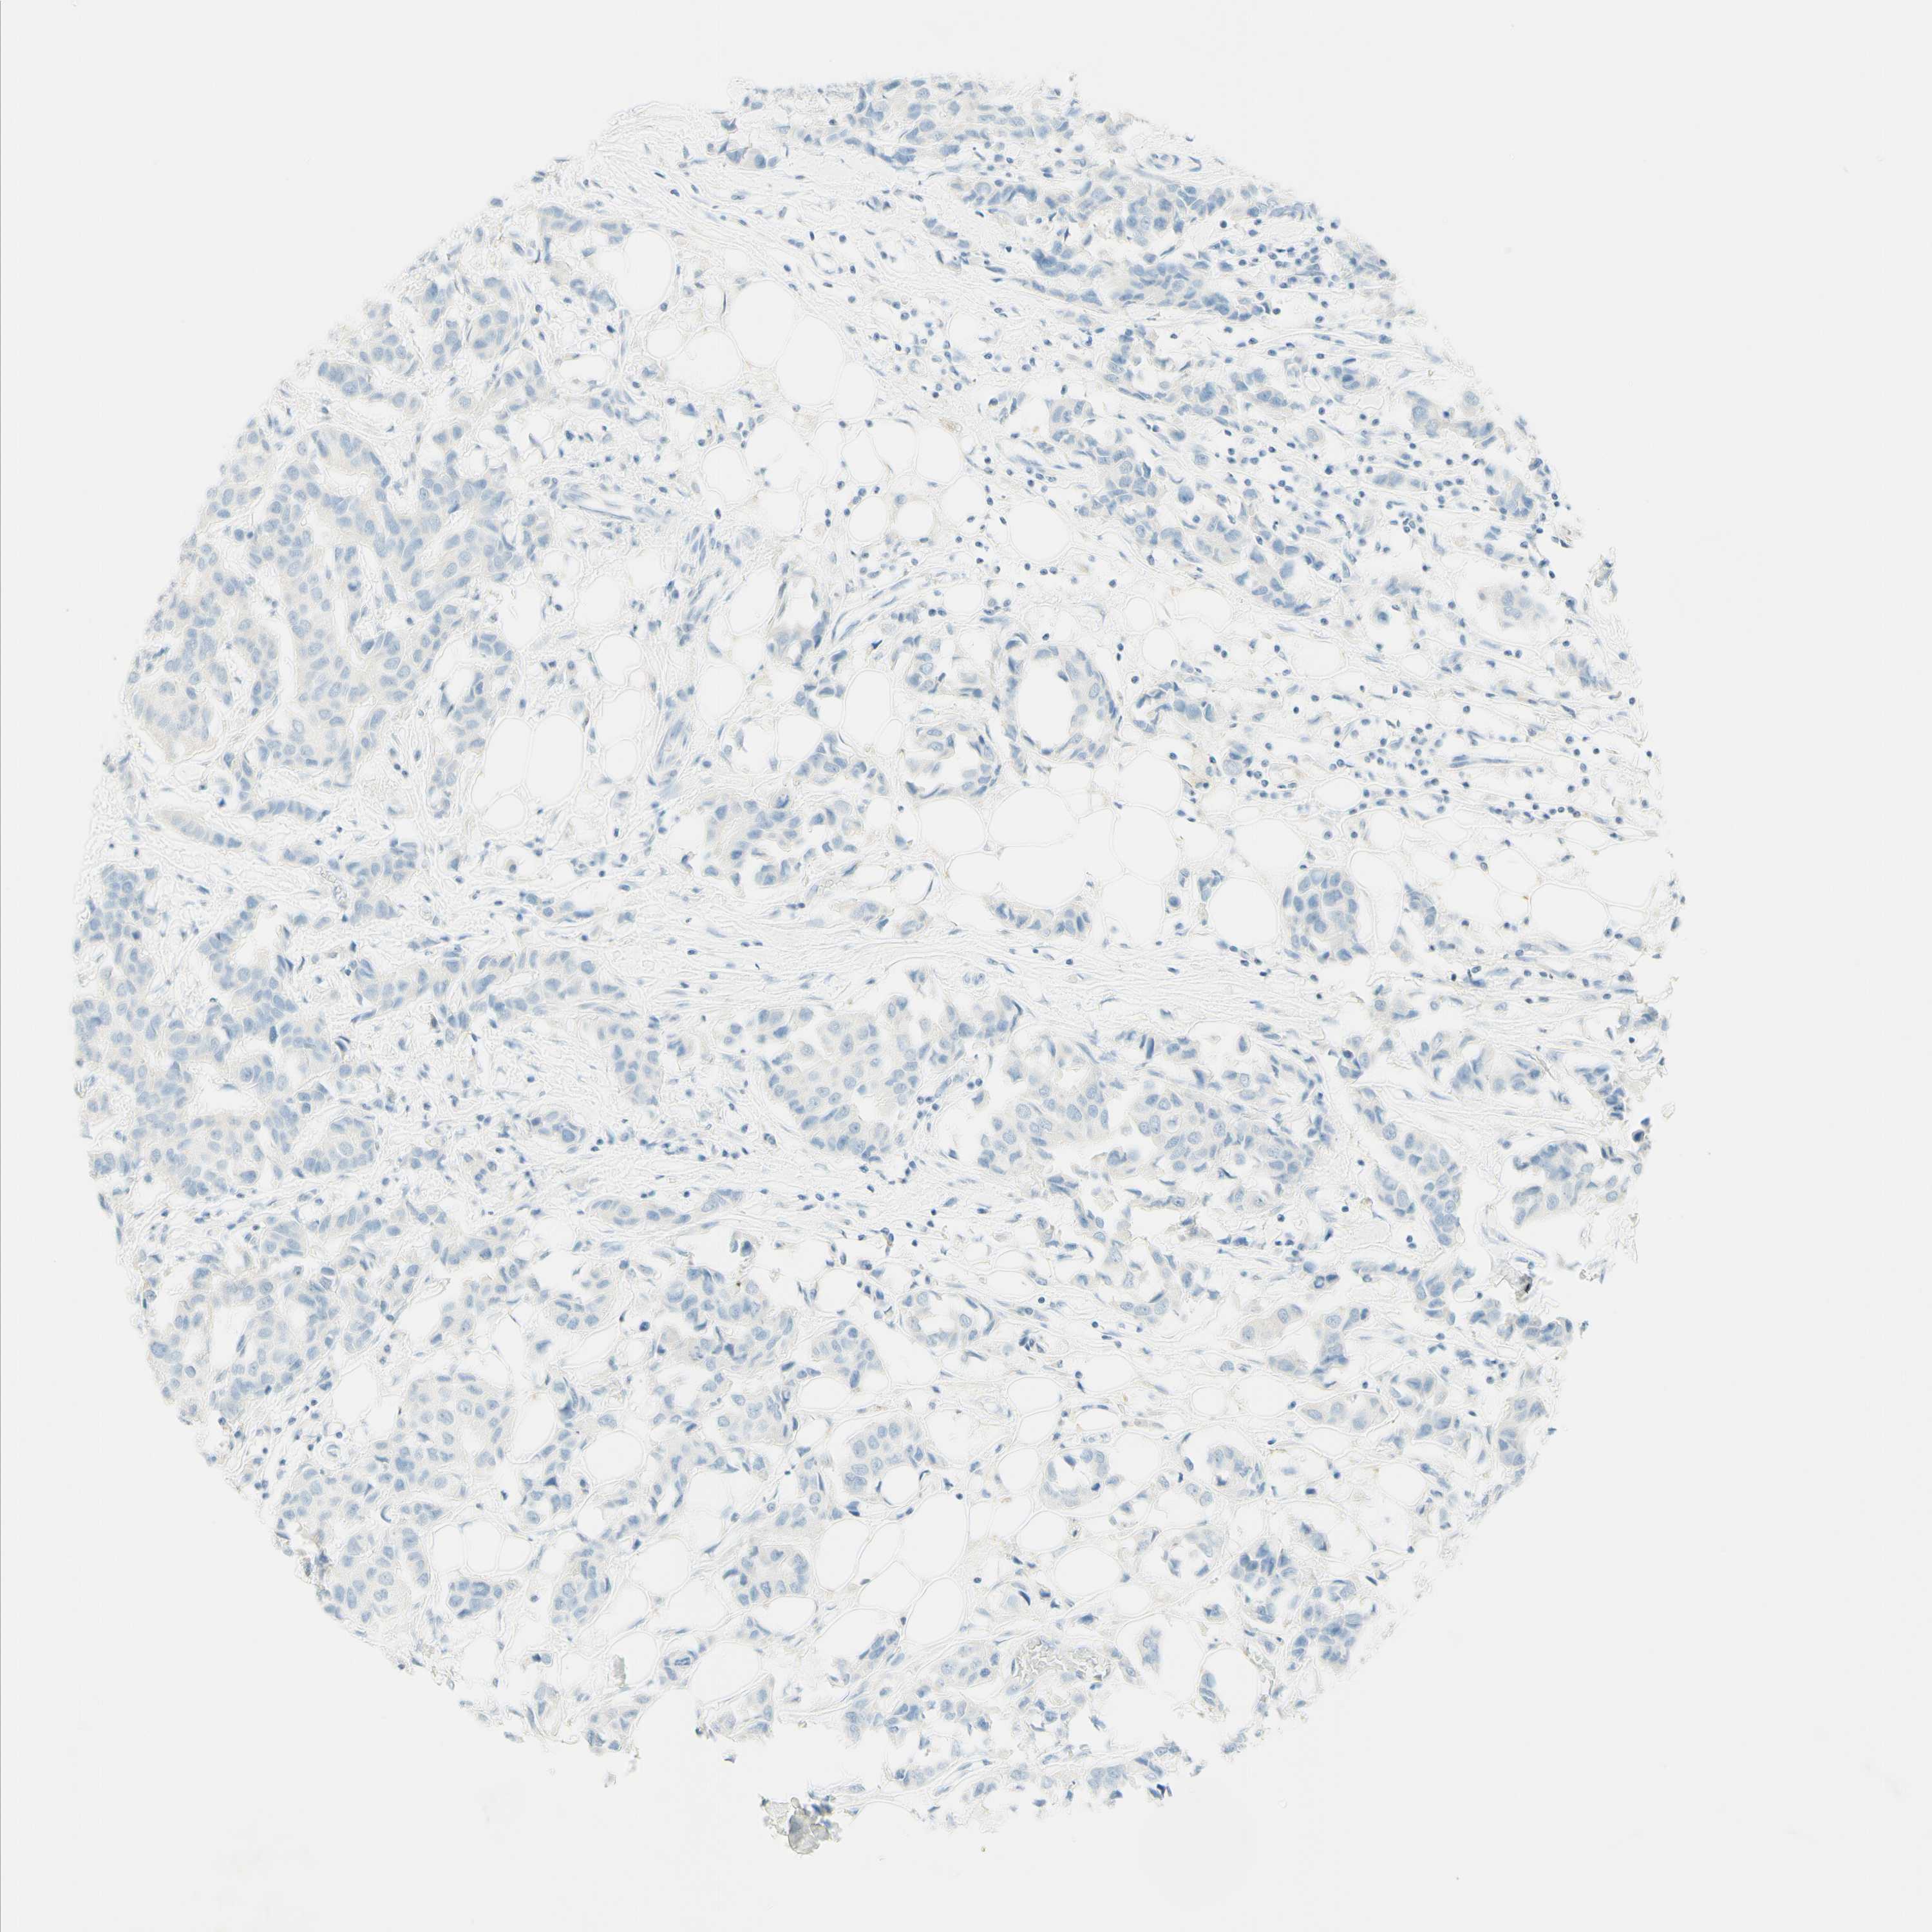

BRCA TCGA BRCA VALIDATION PROTEIN EXPRESSION